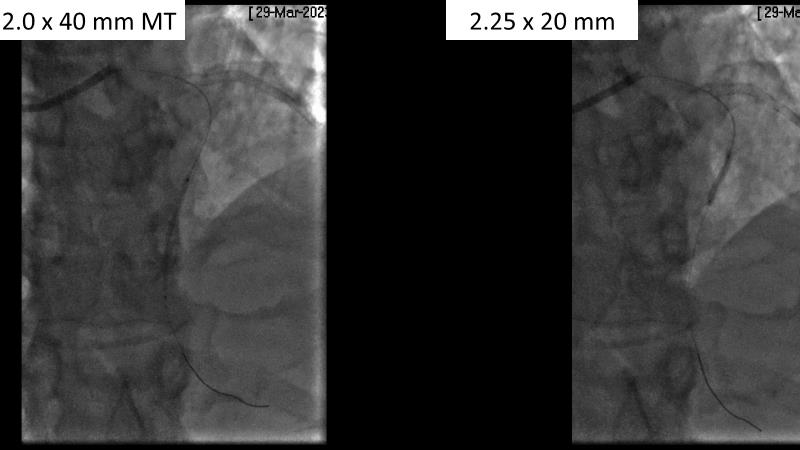

Watch this session to gain case-based insights on using DCBs in complex settings. Learn valuable tips and tricks for optimal DCB application, including the best timing and situations for their use. Discover how to effectively implement a hybrid strategy that combines DES and DCB when needed.

- To get a case based experience on how to use a DCB in complex settings

- To learn about tips and tricks on how and when to use a DCB: the ideal time and situation of DCB application in various complexities

- To utilise the hybrid strategy approach Combining DES and DCB when the situation demands